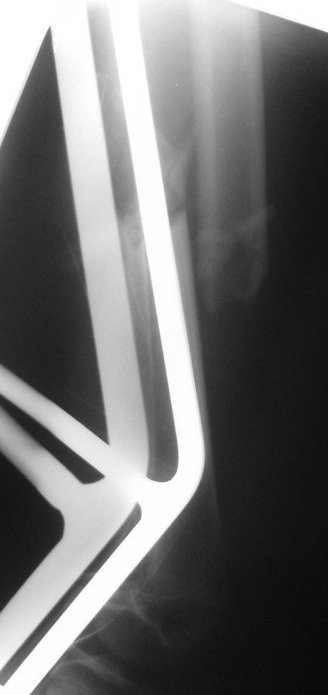

TEN v13 let rabotaet ne ochen:mnogo malunions.Ya by postavil regid IMN.Sudya po snimkam growth plates closed.Luchshe konechno postavit trochanteric nail-net opasnosti AVN.Drugaya opzya posle rastyaghenya(oh namuchaetes!),postavit bridging long plate:prosto ikrasivo.

Переделаем снимки. Мне кажется, что зона роста еще работает, хотя четко сказать нельзя. Да, трохантерный гвоздь 8 мм - тут наверное, самое оптимальное решение. Если возьмемся работать TEN, то возьмем стержни по 3 мм.ИМ канал узкий, в истмусе где-то 8-9 мм. В сумме объем занимаемый TEN заполнит ИМ канал больше чем на 60%, плюс "трехточечная" фиксация, может и сработает и не допустит malunions в дальнейшем.

Я бы сделал свежие. Пока предполагаю, что раз срок большой, возраст маленький, то, вероятно, лучше в два этапа - - аппаратом растянуть за неделю, а потом заштифтовать. Раз старше 12 лет, то согласен с Марком, не TENами, а нетолстым ригидным стержнем с латерализованным проксимальным отделом. Зона роста если и пострадает, то всего одна, и за оставшейся период роста не успеет сформироваться разница длин.